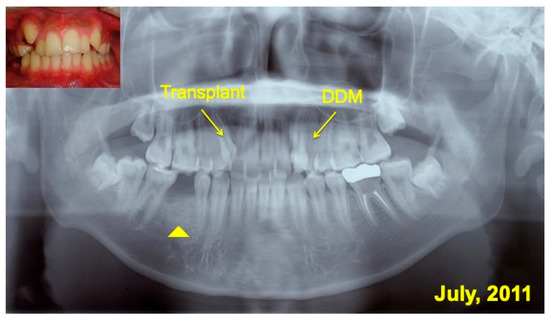

2. Materials and Methods

3. Results

3.2. Radiographic Evaluation